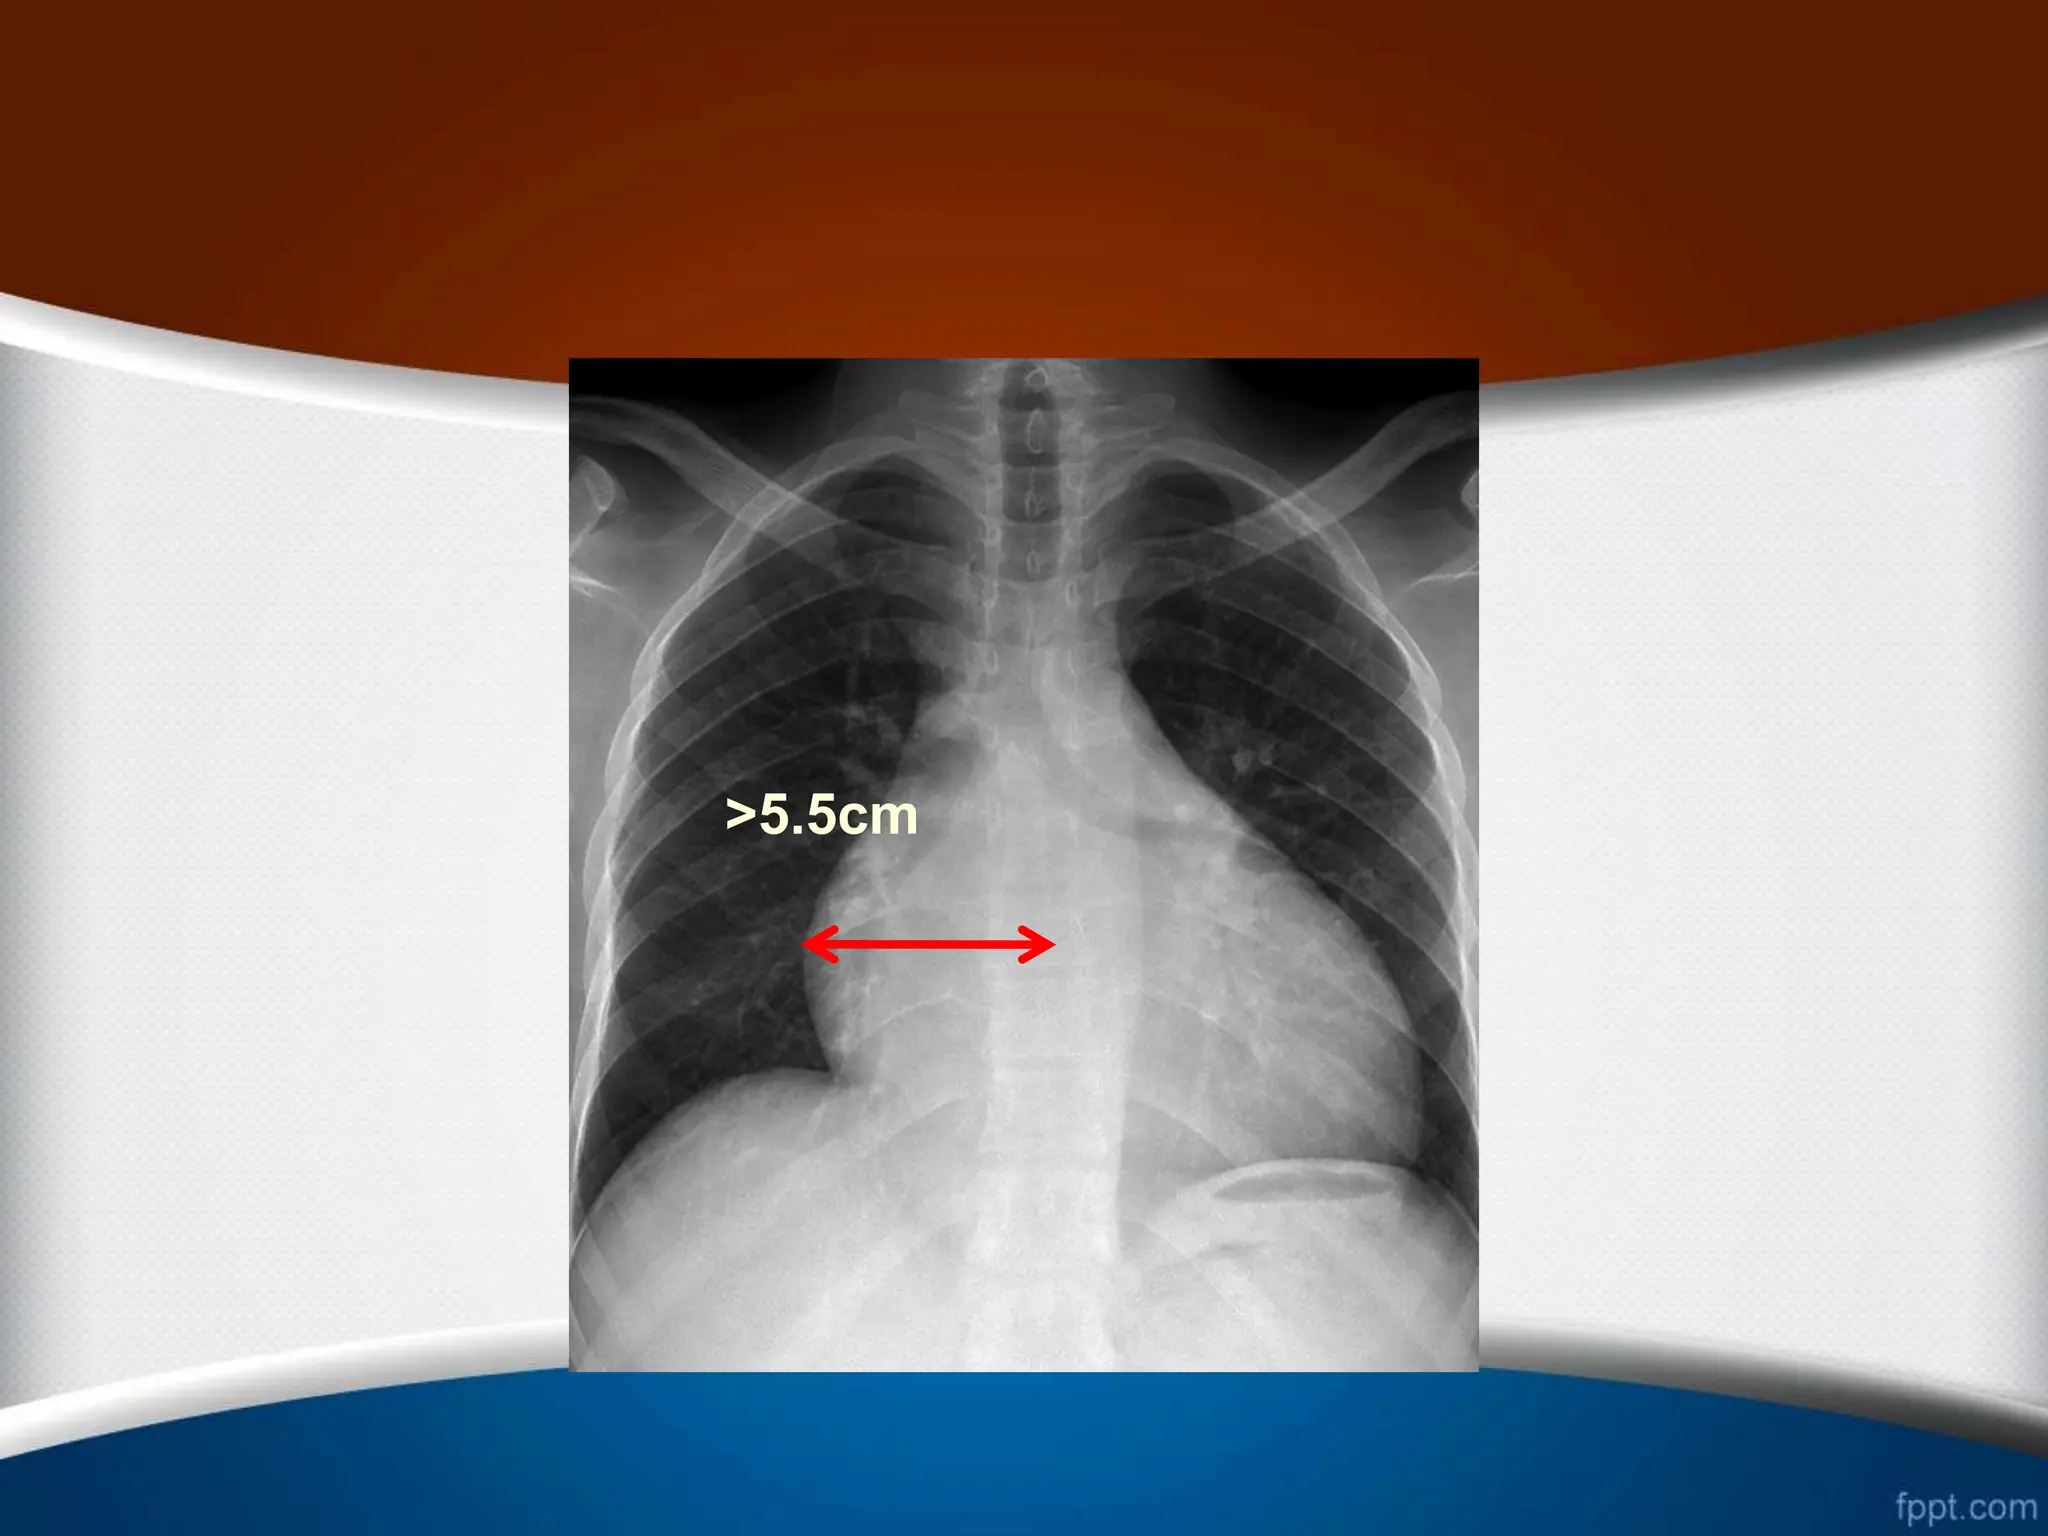

‫راست‬ ‫دهلیز‬ ‫بزرگی‬

.1

‫از‬ ‫بیشتر‬ ‫قلب‬ ‫راست‬ ‫ی‬ ‫کناره‬ ‫افزایش‬

25

%

‫قلب‬ ‫عرضی‬ ‫دیامتر‬

.2

‫راست‬ ‫کاردیوفرنیک‬ ‫ی‬ ‫زاویه‬ ‫شدن‬ ‫باز‬

(

‫منفرجه‬ ‫یا‬ ‫قائمه‬

)

.3

‫از‬ ‫بیشتر‬ ‫وسط‬ ‫خط‬ ‫از‬ ‫راست‬ ‫دهلیز‬ ‫ی‬ ‫حاشیه‬ ‫بین‬ ‫ی‬ ‫فاصله‬

5.5

‫از‬ ‫بیشتر‬ ‫ها‬ ‫مهره‬ ‫ستون‬ ‫راست‬ ‫حاشیه‬ ‫از‬ ‫و‬ ‫متر‬ ‫سانتی‬

2.5

‫متر‬ ‫سانتی‬

.

.4

‫می‬ ‫تشکیل‬ ‫را‬ ‫توراکس‬ ‫همی‬ ‫سوم‬ ‫یک‬ ‫از‬ ‫بیشتر‬ ‫راست‬ ‫دهلیز‬

‫دهد‬

.5

‫راست‬ ‫دهلیز‬ ‫و‬ ‫صعودی‬ ‫آئورت‬ ‫و‬ ‫راست‬ ‫دهلیز‬ ‫بین‬ ‫ی‬ ‫زاویه‬

‫شود‬ ‫می‬ ‫واضح‬

>5.5cm

>2.5cm

>25%

>1/3